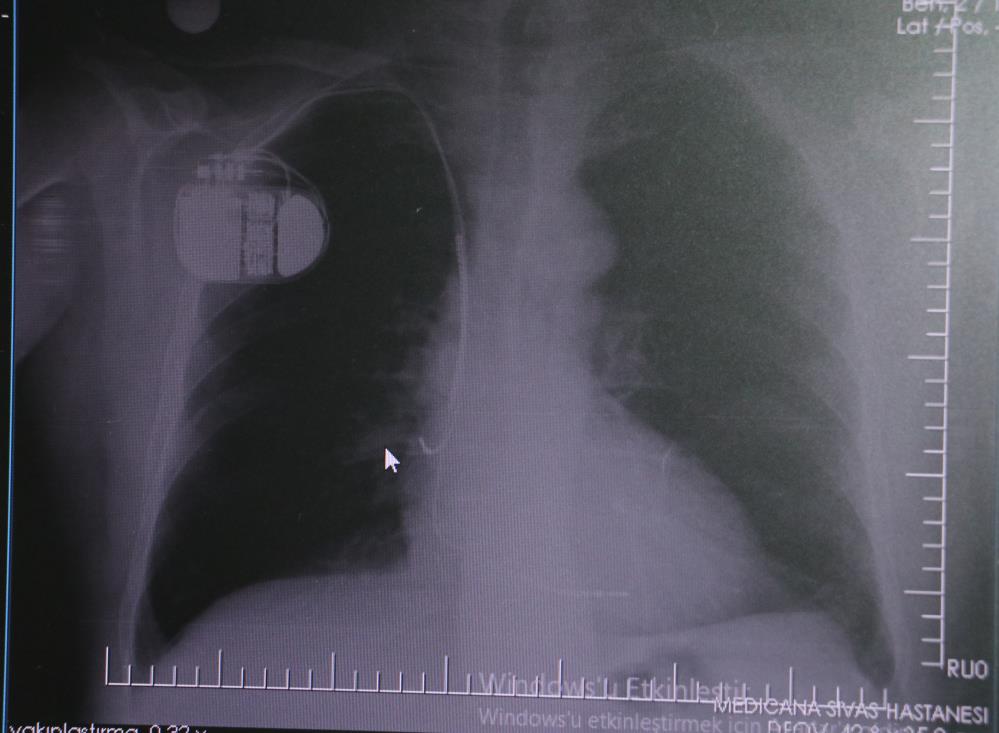

Kalp pilleri ile MR cihazına girilebileceğini belirten Erdoğu, "Çok büyük bir ameliyat değil ama yine de ciddi bir cerrahi işlem. Kalp pili, tıpta son 30 yılda yaşanan gelişmelerden en büyüğü. Bir bilgisayarın küçültülüp insan vücuduna konulmuş hali aslında. İnsan ömrünü ciddi oranda uzatan bir tedavi. İnsanlar bir şokla hayata tutunurken, pil olmasaydı öleceğini düşündüğümüz birçok hastamız var. Kalp pilinin bu özelliği, uygun hastalarda ciddi oranda ani ölümü engelliyor. Hastanın başına gelecek bir kalp durması durumunda yanında bir sağlıkçı yoksa, onun ritmini düzeltecek defibrilatör cihazı yoksa hastayı hayatta tutmak mümkün değil. Uygun endikasyonlarda kalp pili olduğu zaman, pil hastaların ritmini algılıyor ve acilde yapılan şoklamayı yaparak hastayı hayata döndürüyor. Kalp pillerinde yeni teknolojilerle MR'a girmek mümkün, tomografiye zaten girebiliyorlar. Tarama cihazlarından geçmelerini uygun görmüyoruz. Bu tarz durumlarda hastalarımız 'kalp pilim var' dediğinde muaf tutuluyorlar. Kalp pilleri ciddi teknolojik cihazlardır. Vücudun içindeki titreşimi, örneğin mikser kullanmak, kolunu sallayacak herhangi bir eylem kalp pilinde olumsuz etki oluşturabilir. Soğuk havalarda vücutta oluşan ciddi titremeler kalp pilinin hafızasını karıştırıp kalbin durduğunu düşündürebilir ve gereksiz şoklama yapabilir. Bu tarz kişilerin soğuk havalarda daha temkinli olması gerekir" diye konuştu.